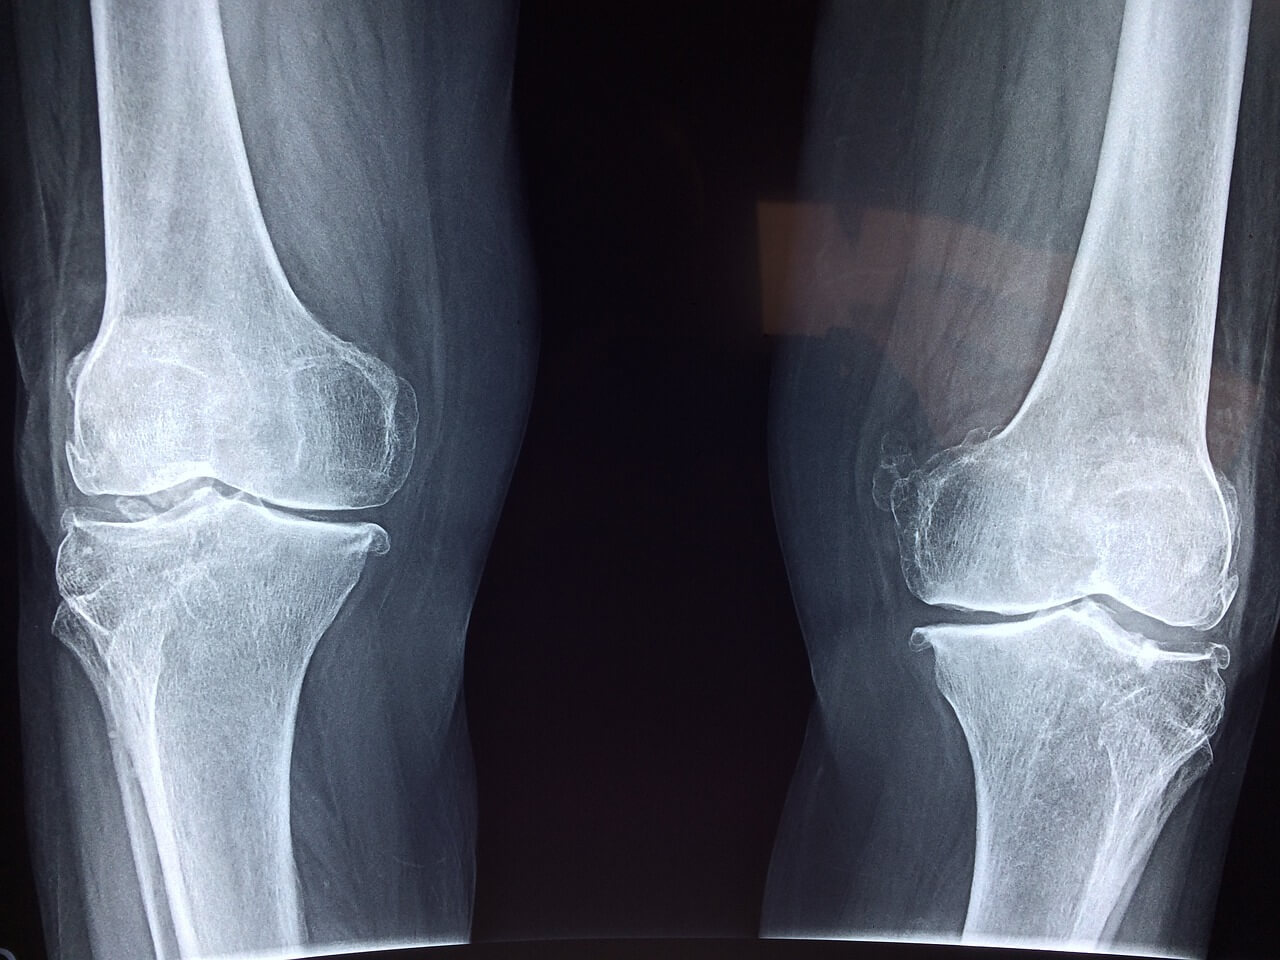

관절 엑스레이 사진무릎 관절 치료점프 띠는 여성

골다공증은 낮은 골밀도와 뼈조직의 악화를 특징으로 하는 질환입니다.

이로 인해 뼈가 약해지고 뼈에 구멍이 생겨 골절에 취약해질 수 있습니다.

골다공증은 점진적으로 진행되는 경우가 많으며 골절이 발생할 때까지 뚜렷한 증상이 나타나지 않는 경우가 많습니다.

가장 흔한 골절은 고관절, 척추, 손목에 발생하며 특히 고령자에게는 심각한 결과를 초래할 수 있습니다.